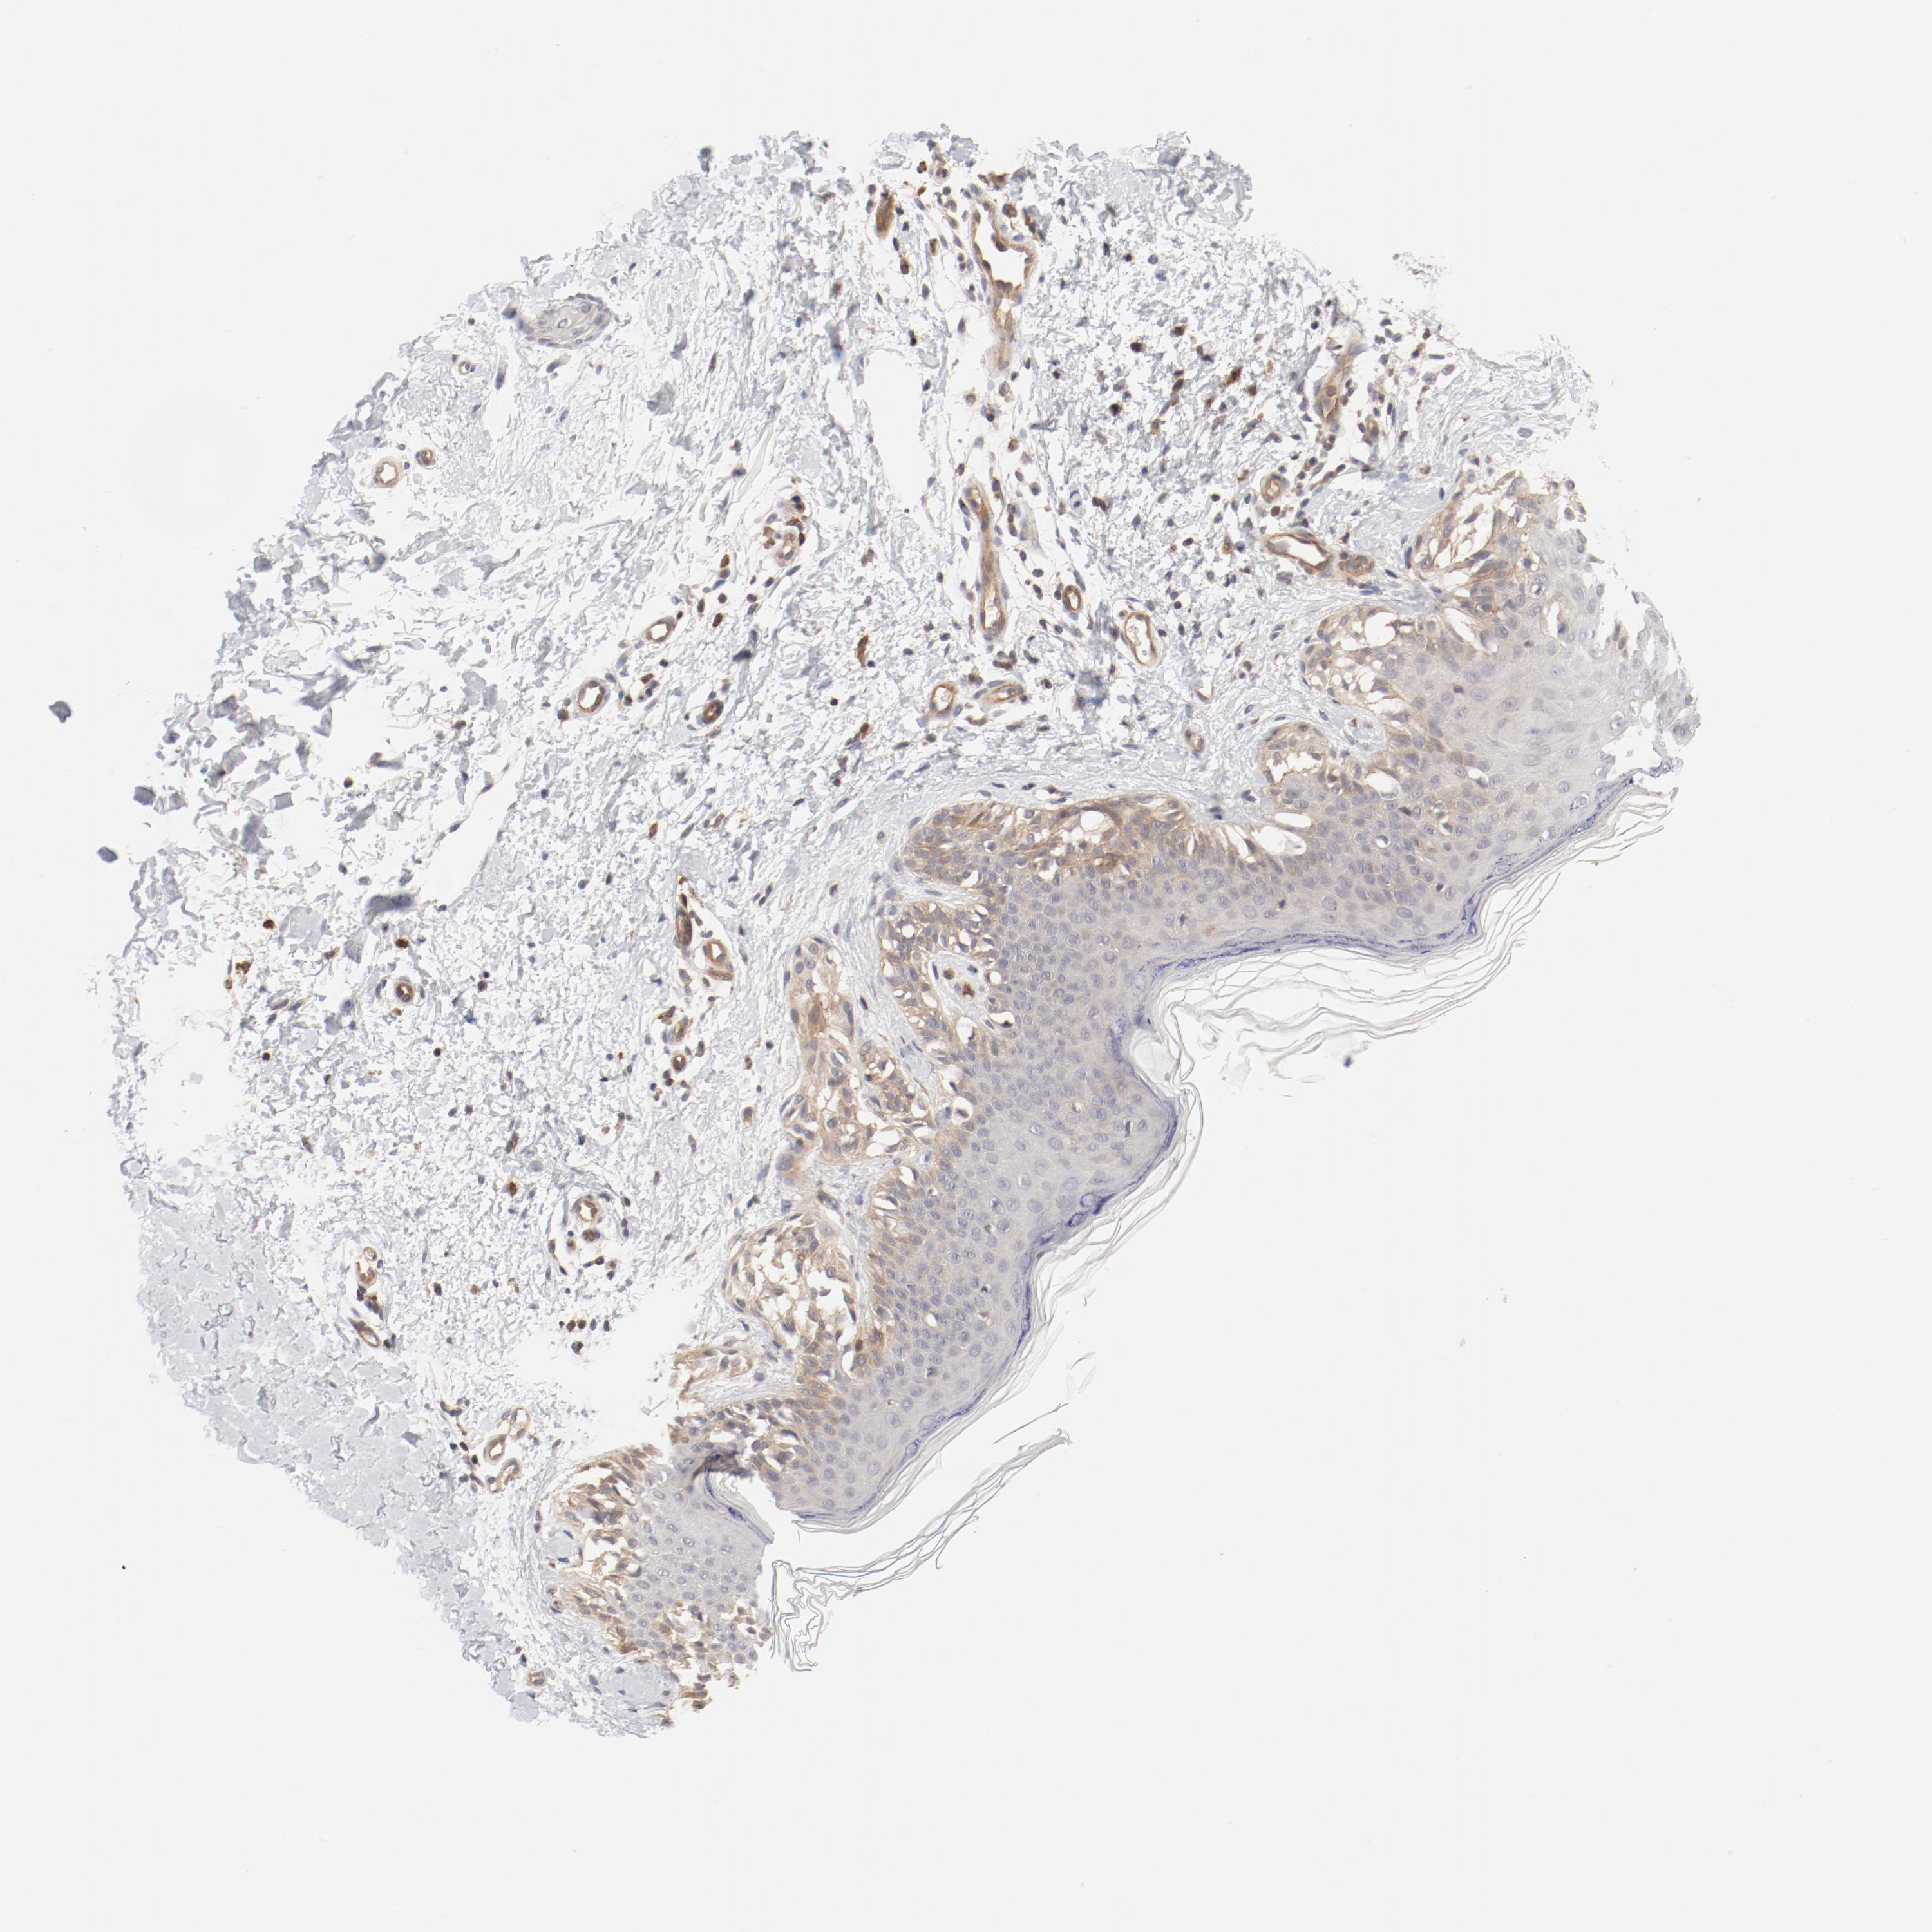

MELANOMA - Protein expressioni

A mouse-over function shows sample information and annotation data. Click on an image to view it in a full screen mode. Samples can be filtered based on level of antibody staining by selecting one or several of the following categories: high, medium, low and not detected. The assay and annotation is described here.

Note that samples used for immunohistochemistry by the Human Protein Atlas do not correspond to samples in the TCGA dataset.

Antibody stainingi

Antibody staining in the annotated cell types in the current human tissue is reported as not detected, low, medium, or high, based on conventional immunohistochemistry profiling in selected tissues. This score is based on the combination of the staining intensity and fraction of stained cells.

Each image is clickable and will lead to virtual microscopy that enables deeper exploration of all samples and also displays staining intensity scores, fraction scores and subcellular localization as well as patient and tissue information for each sample.

Antibody HPA003866

Staining

High

Medium

Low

Not detected

Intensity

Strong

Moderate

Weak

Negative

Quantity

>75%

75%-25%

<25%

None

Location

Nuclear

Cytoplasmic/membranous

Cytoplasmic/membranous,nuclear

Malignant melanoma, Metastatic site